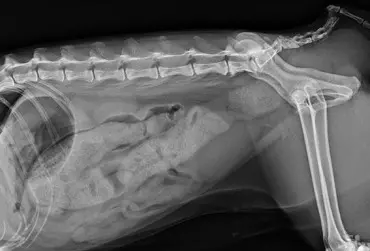

Torbiel pierwotna jelita prostego u kota rasy Manx. Opis przypadku

Torbiel pierwotna jest rzadką wadą rozwojową występującą u człowieka, psa, kota i konia. W niniejszym artykule opisano przypadek torbieli pierwotnej jelita prostego u dziewięcioletniego kota rasy Manx, u którego występowały przewlekłe zatwardzenia. W badaniu rektalnym i radiograficznie stwierdzono obecność miękkiego guza dogrzbietowo i bocznie od jelita grubego. Badaniem ultrasonograficznym i w tomografii komputerowej uwidoczniono dobrze odgraniczoną, cienkościenną torbiel, częściowo zamykającą światło kanału miednicy. Torbiel usunięto chirurgicznie z dojścia okołoodbytowego. Nie stwierdzono połączenia torbieli ze ścianą prostnicy. Badanie histopatologiczne potwierdziło postawione podejrzenie torbieli pierwotnej. Po wykonanym zabiegu objawy kliniczne całkowicie ustąpiły.